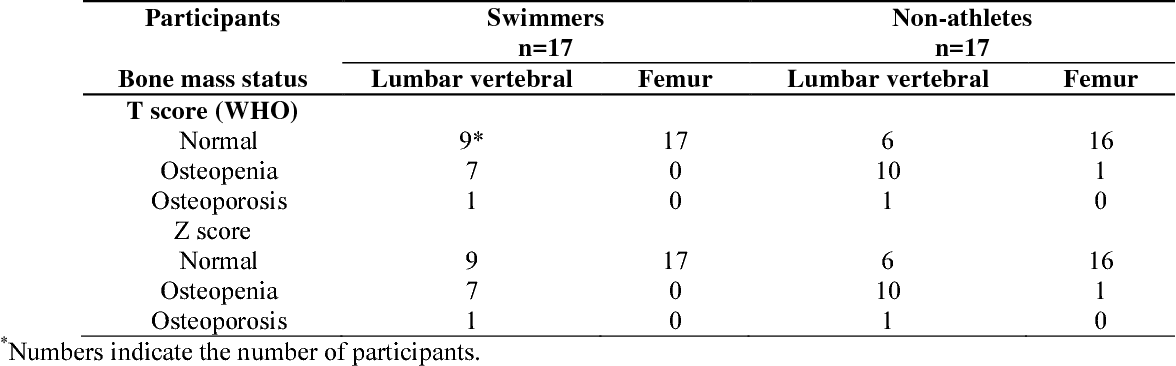

Figure 1 From The Comparison Of BMC BMD T Score And Z Score Of The

Figure 1 From The Comparison Of BMC BMD T Score And Z Score Of The